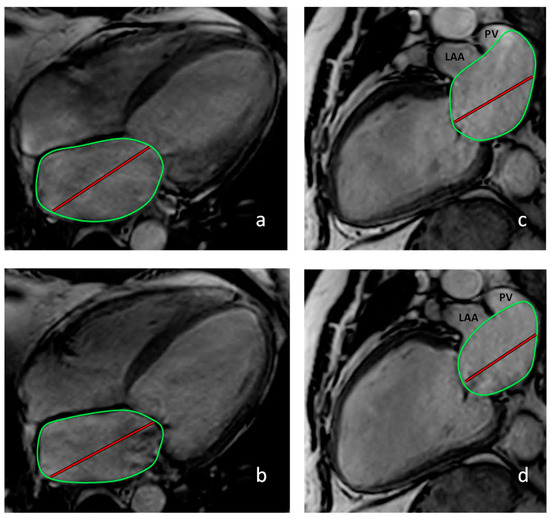

The left atrial ejection fraction (LAEF) was calculated by subtracting maximal and minimal LAV divided by maximal LAV multiplied by 100 (100 × [(LAVES − LAVED)/LAVES]; Figure 1) [16]. As previously described, the left atrioventricular coupling index was calculated by dividing the LAVED by the LVEDV and expressed as a percentage [17]. RHC was performed according to standard recommendations [18], either alone or combined with coronary angiography using an Edwards Lifesciences Vigilance II™ monitor or the Schwarzer Cardiotek Evolution system. Cardiac output (CO) was measured using the thermodilution method [19]. In eight patients with missing CO values according to the thermodilution method, CO was estimated using the indirect Fick method, as suggested by Krakau [11].

Figure 1. Calculation of the left atrial ejection fraction. Calculation of LA volume based on the 4-chamber (CH) view (a,b) and the 2-CH view (c,d). Abbreviations: LAA: left anterior appendage; PV: pulmonary vein. (a) End-systolic 4-CH view. (b) End-diastolic 4-CH view. (c) End-systolic 2-CH view (LAA and PV were excluded from the atrial area). (d) End-diastolic 2-CH view (LAA and PV were excluded from the atrial area; green circles correspond to the LA-area, red line to the LA-length).